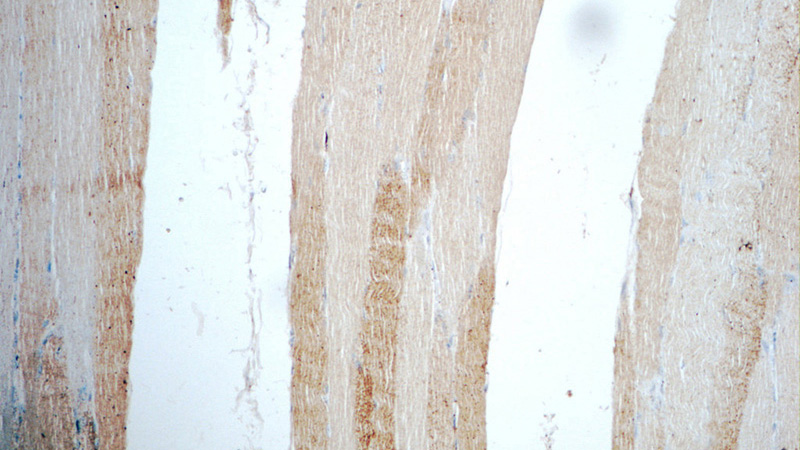

Immunohistochemistry of paraffin-embedded human skeletal muscle tissue slide using Catalog No:107771(ADAMTSL4 Antibody) at dilution of 1:50 (under 10x lens)